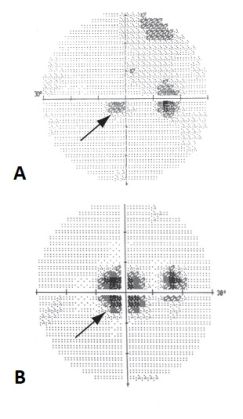

MAR is a paraneoplastic syndrome that typically presents after the diagnosis of melanoma. This condition primarily affects individuals with metastatic cutaneous or uveal melanoma and manifests as progressive, bilateral, and painless visual deterioration[1][2]. The visual symptoms generally include a sudden onset of shimmering, flickering photopsias, night blindness, and progressive vision loss over several months, with characteristic peripheral visual field depression or mid-peripheral visual field loss[3].

The pathophysiology of MAR is centered around the autoimmune response against retinal antigens. Specifically, the antiretinal antibodies in MAR primarily target the bipolar cells[2], which is evident from electroretinography findings showing a marked reduction in the b-wave. This indicates compromised bipolar cell function while the photoreceptor cell function remains relatively normal, leading to an electronegative ERG[4]. This selective involvement contributes to the characteristic visual symptoms associated with MAR.

MAR should be suspected in a patient with the characteristic signs and symptoms and a known history of melanoma. The diagnosis is supported by findings from visual field tests and electroretinography. MAR is classically defined as a triad[2] of:

- nyctalopia, positive visual phenomena, and/or visual field defects

- electronegative ERG

- serum autoantibodies that are reactive with retinal bipolar cells

- ERG is essential for assessing the functionality of the retinal cells, specifically showing reductions in the b-wave amplitude[4].